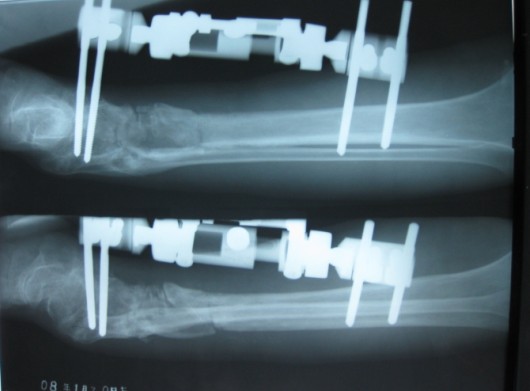

骨瓣移植术后

骨瓣移植术后一年半